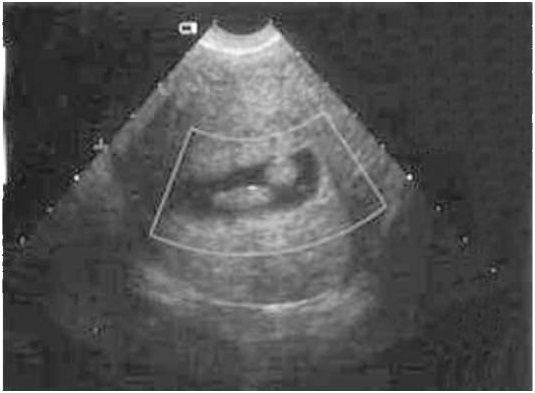

Изображение полипов на экране УЗИ

Характерным проявлением эндометрических полипов является изоэхогенная структура. Но наличие в них фибриновых нитей увеличивает эхоплотность включения. На экране они похожи на эндометрий. При поперечном методе сканирования отличаются от эндометрических включений ровными круглыми контурами.

Полипы